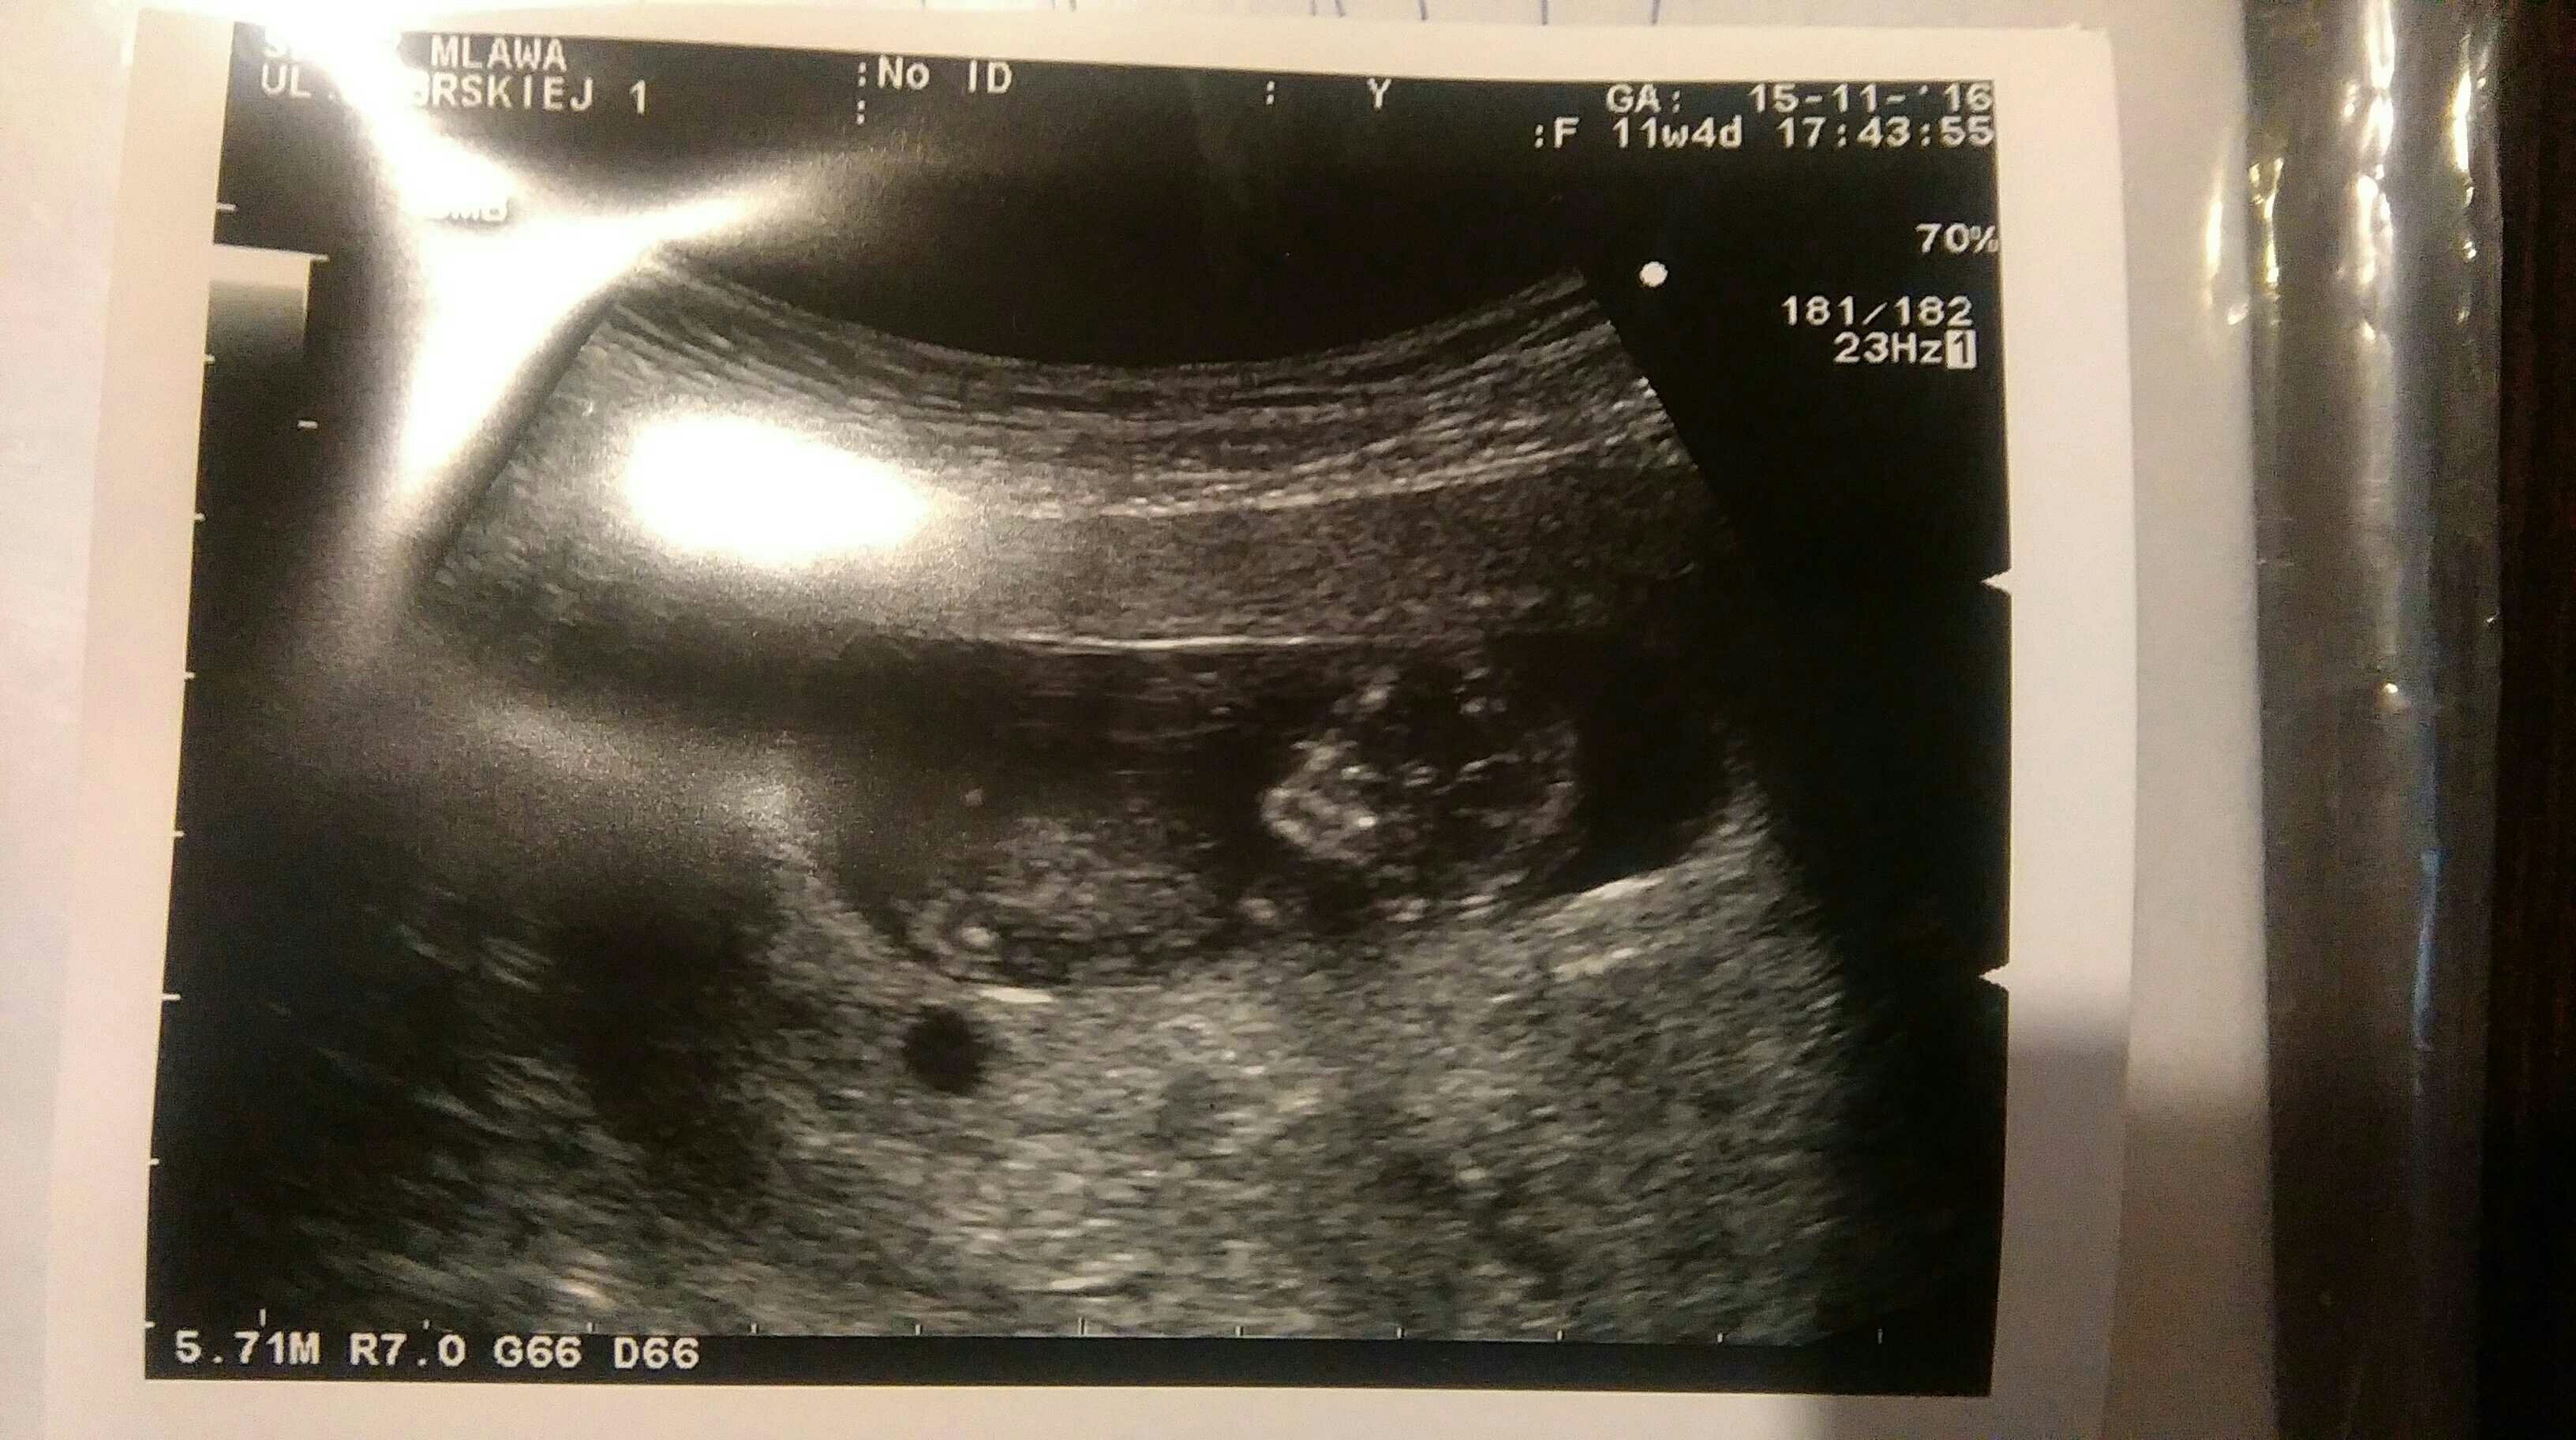

Dziewczynki ja już po USG. Dzidziuś zdrowy! Parametry IDEALNE, kość nosowa: JEST, przezierność: 0,9. To był miód na moje uszy [emoji7] Widziałam jak się rusza, był odwrócony pleckami. Maluszek wyszedł idealnie: z USG i OM tyle samo! Poprosiłam o jedną fotkę dzidziusia, żeby pokazać chłopcom i dobrze że to zrobiłam bo dołączyła tylko paramerty. Zobacz załącznik 783030 Jestem mega szczęśliwa, jem kebaba i pije turecką herbatkę z imbirem u znajomego który dla mnie robi miksy swoich potraw (wedle zachcianki hihi)